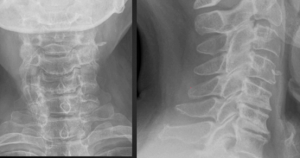

2. Limbus Bone

A limbus bone is an unfused secondary ossification center of the vertebral body (typically the anterosuperior corner), due to herniation of the nucleus pulposus through the ring apophysis prior to skeletal development. This fragment remains ununited to the vertebral body throughout the patient’s life. This can be differentiated from a fracture in that it is well-corticated, triangular, and the fragment of bone will not exactly “fit” into the defect. These fragments may be smaller than the defect of the bone (figure 2) or they may hypertrophy over time and become larger (figure 3). A limbus bone is most often asymptomatic.